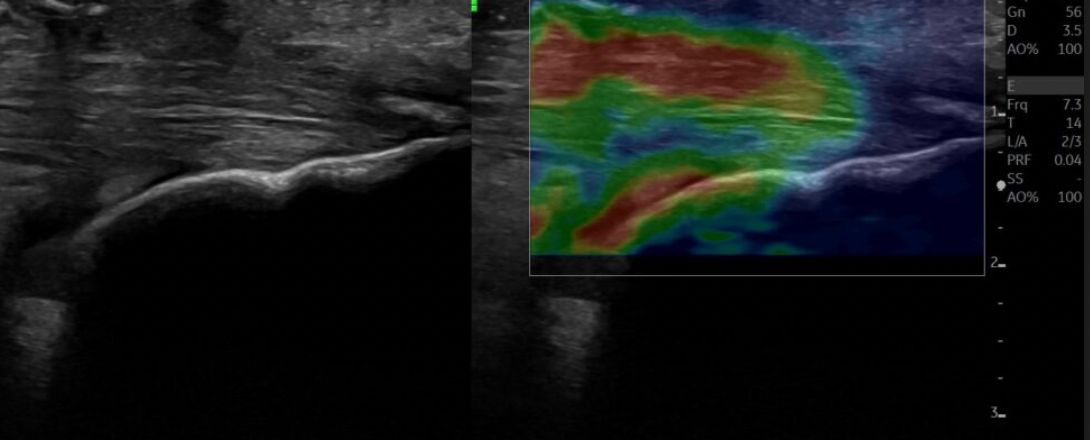

Ho concentrato la mia attività in radiologia diagnostica ed interventistica in campo muscolo-scheletrico, con particolare attenzione alle patologie reumatologiche, oncologiche, infettive e sportive, senza tralasciare i restanti campi della radiologia tradizionale, trattando anche patologie di addome, torace e tiroide.

Attualmente svolgo la professione da dirigente medico come pubblico impiego ed in privato in alcune strutture specializzate nella diagnostica e nel trattamento della patologia muscolo-scheletrica, potendo così esercitare una diagnostica completa, comprendente Ecografia, Radiografia (RX), Tomografia Computerizzata (TC) e Risonanza Magnetica (RM).

Dopo una diagnostica accurata (imprescindibile una corretta diagnosi), eseguo tramite guida radiologica ed ecografica terapia infiltrativa muscolo-scheletrica, tecnica ormai dimostrata negli anni in letteratura scientifica essere più efficace e sicura della classica terapia infiltrativa non eco-guidata.  Collaboro inoltre ogni giorno con ortopedici, terapisti del dolore e fisioterapisti per garantire al paziente una cura completa ed un approccio multidisciplinare alla patologia.

• Ecografia

• Ecografista